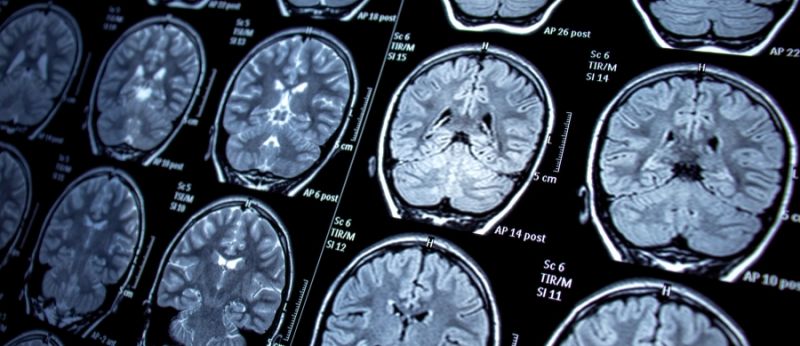

A condição é uma alteração temporária e reversível do funcionamento do cérebro, que não tem relação com febre, drogas ou distúrbios metabólicos. Além disso, ela se expressa por crises epilépticas repetidas.